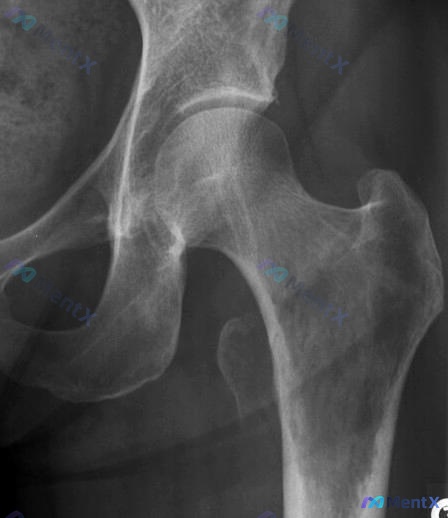

病例讨论:51 岁男性左髋疼痛 整理到一个病例资料,想听听大家的看法。 基本信息: - 性别:男 - 年龄:51 岁 - 主诉:左臀部疼痛 影像所见(左侧髋关节正位 X 光片): 1. 骨质密度: 股骨近端及髋臼周围骨密度减低,呈斑片状改变,骨小梁结构较为模糊。 2. 关节间隙: 维持尚可,未见明显...